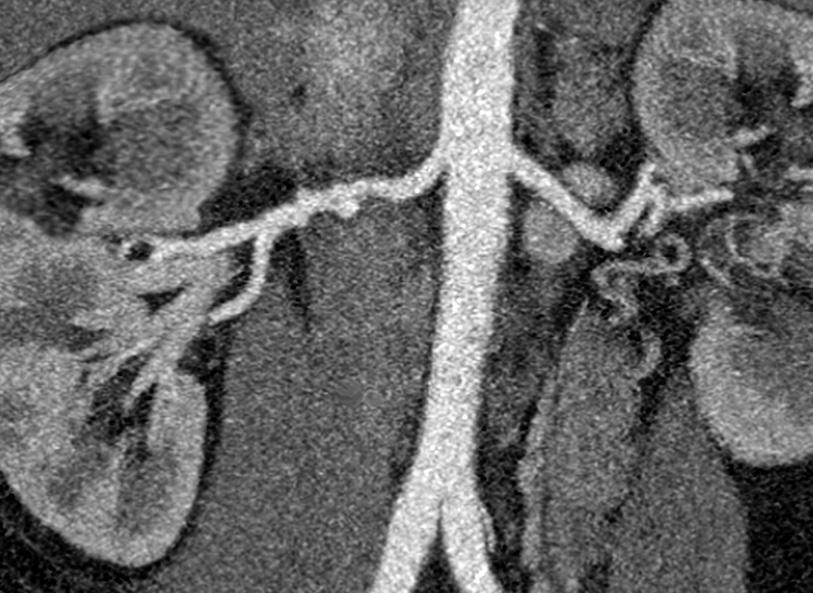

The “string of beads” appearance typical of fibromuscular dysplasia in the right renal artery (at left) visible on a coronal computed tomography angiogram scan.